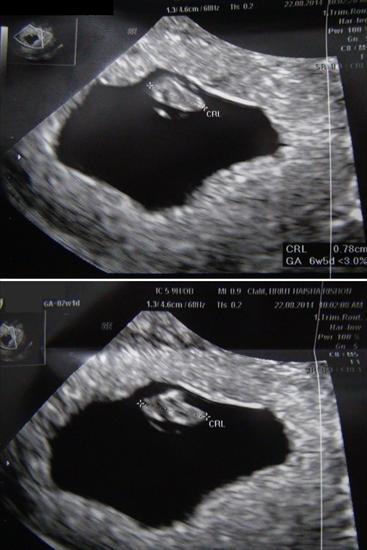

I did a vaginal ultrasound

WEEK 7 + 1

Testing: Vaginal

What is the gender of the fetus?Attachment 20539

I'm no expert....my guess based on what I've read and by imagining the picture on a belly facing out would be girl.